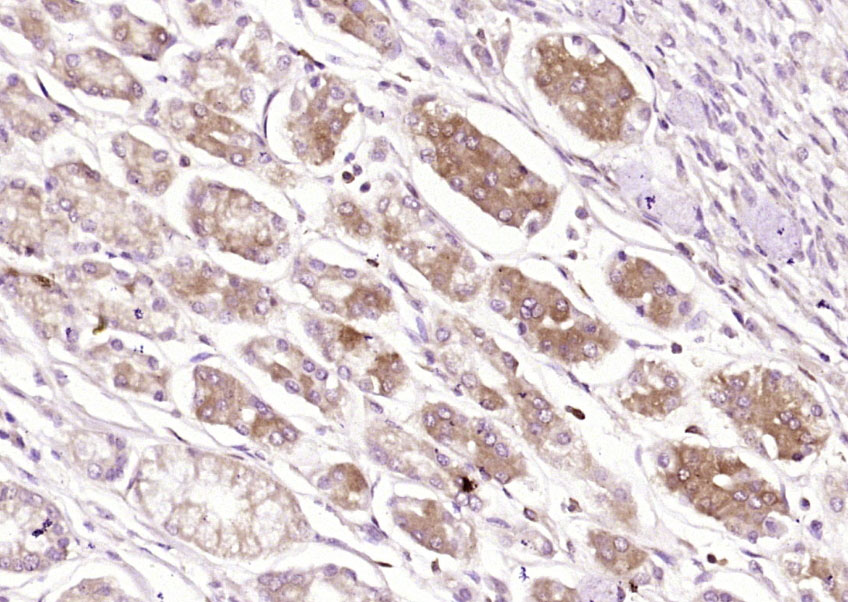

Paraformaldehyde-fixed, paraffin embedded (human pancreatic cancer); Antigen retrieval by boiling in sodium citrate buffer (pH6.0) for 15min; Block endogenous peroxidase by 3% hydrogen peroxide for 20 minutes; Blocking buffer (normal goat serum) at 37°C for 30min; Antibody incubation with (SSTR4) Polyclonal Antibody, Unconjugated (bs-21862R) at 1:200 overnight at 4°C, followed by operating according to SP Kit(Rabbit) (sp-0023) instructionsand DAB staining.